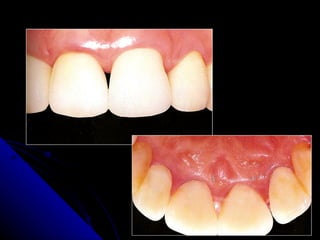

O  término cervical  do preparo deve ser bem definido, coerente ao tipo do material empregado e com bom acabamento.  Coroa provisória  bem adaptada e com contornos corretos. Presença de  saúde periodontal PEGORARO, L. F. 1999

O términocervical do preparo deve ser bem definido, coerente ao tipo do material empregado e com bom acabamento. Coroa provisória bem adaptada e com contornos corretos. Presença de saúde periodontal PEGORARO, L. F. 1999

LIMITE CERVICAL Evidencias  científicas  mostram as  limitações na promoção da saúde periodontal , quando o  limite cervical  das restaurações protéticas estão em  contato com os tecidos gengivais.

Margem Cervical O  ideal periodontal  é que as margens protéticas  não sejam  colocadas em contato gengival. Quando  necessário  seja num limite apical que o paciente possa facilmente controlar  a placa bacteriana – até  0,5mm subgengival.

LIMITE CERVICAL  Nas   restaurações subgengivais  com muita freqüências observa-se inflamação gengival, placa bacteriana e formação de bolsas periodontais .